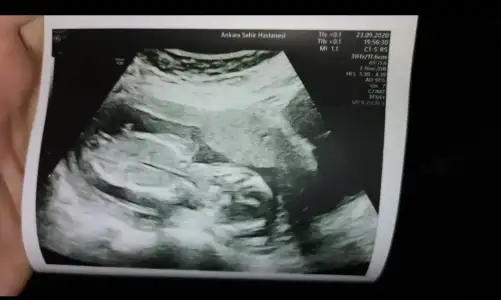

Mrb tahmin edebilir misiniz rica etsem🙏🏻🙏🏻🙏🏻🙏🏻

Eklentiler

• IMG_20200922_210453.webp

IMG_20200922_210453.webp

24,3 KB · Görüntüleme: 50

• IMG_20200922_210511.webp

IMG_20200922_210511.webp

20,1 KB · Görüntüleme: 52

Merhaba bende normalde 11+2yim bir hafta önde demişti doktor ikiz bekliyorum kısmetse benimkilere de bakabilir misiniz🤗 Ikra meyra Ikra meyra

• IMG_20200922_210915.webp

IMG_20200922_210915.webp

15,1 KB · Görüntüleme: 64

Kaç haftalık USG ler büyük sanki 11 12 13 haftalar olmalı.sanki kız emin olamadım istediğim haftalar varsa paylaşın